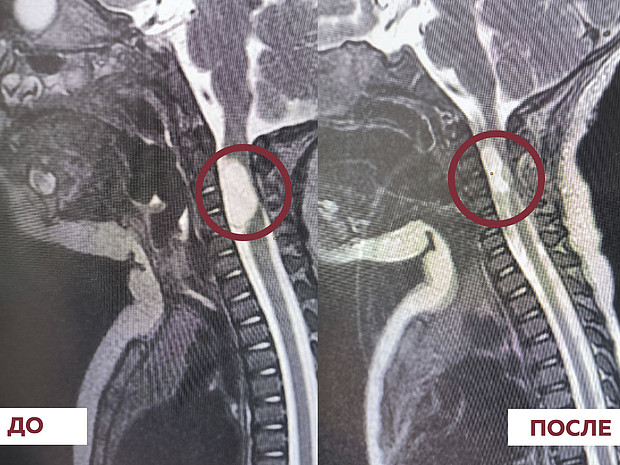

Необычную травму молодой человек получил в дорожной аварии